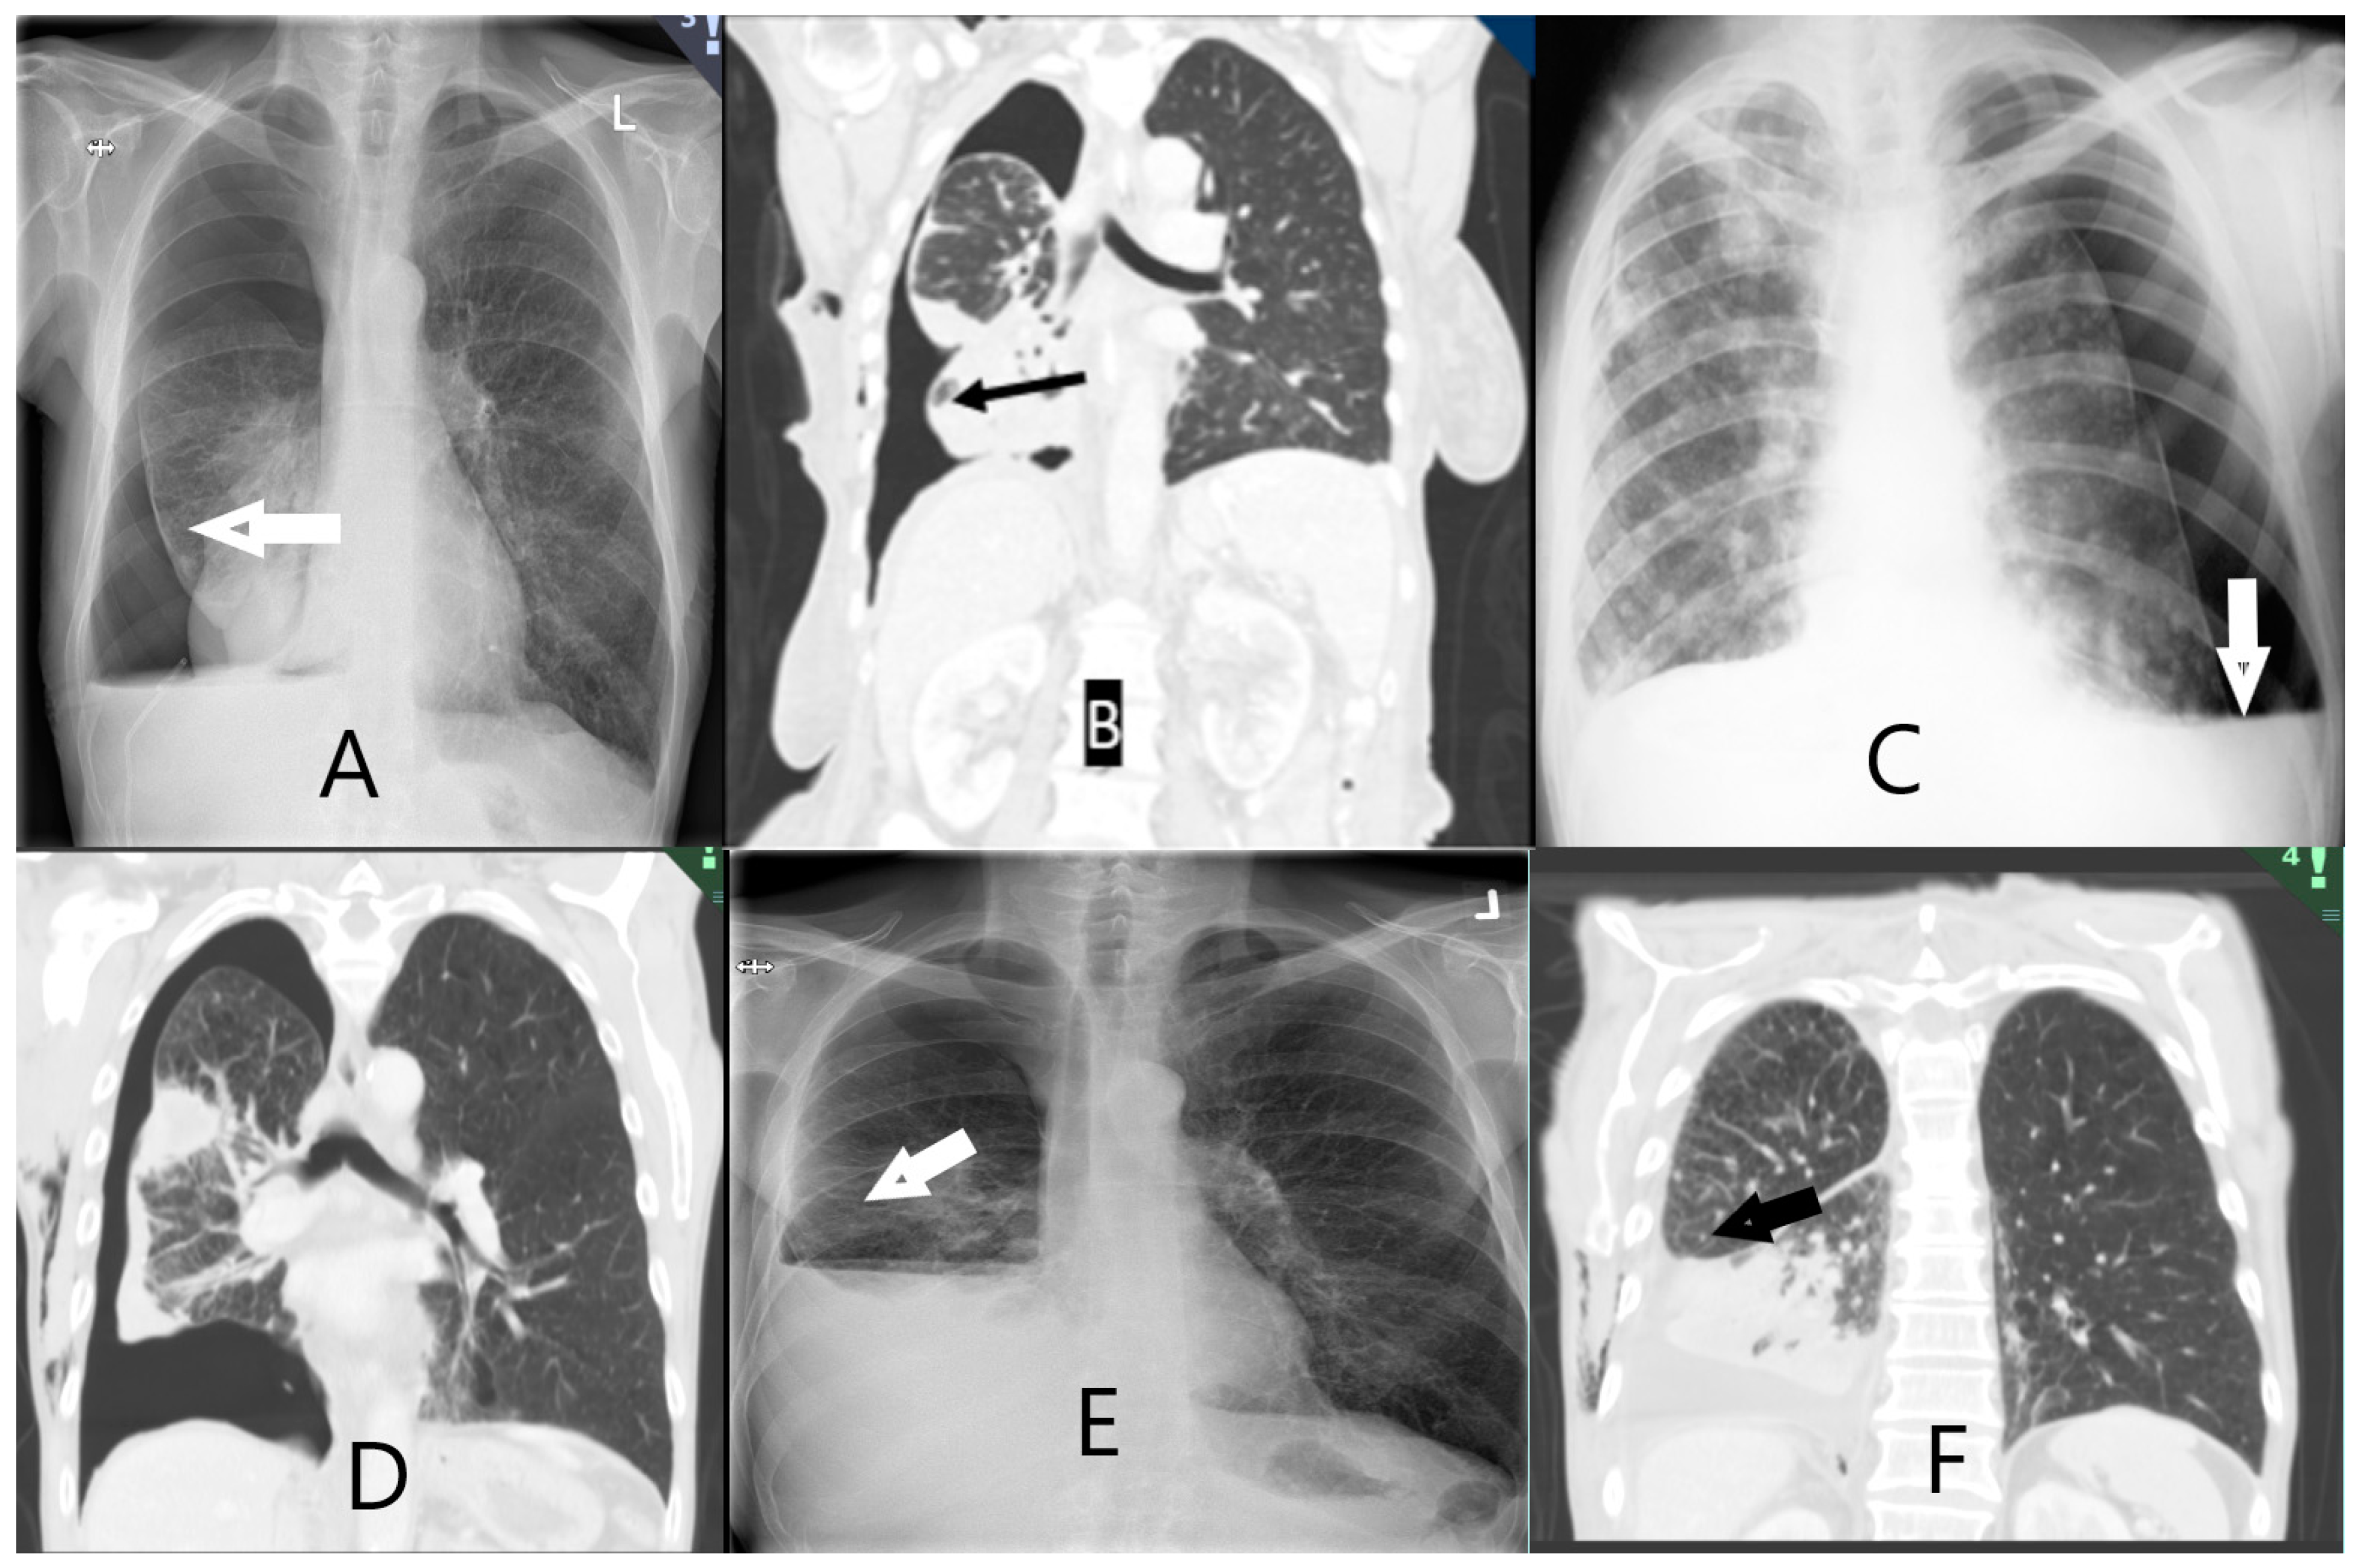

| Entrapped lung scoring on chest X-ray or chest CT scan | |

| A. Definitely free. Complete apposition of parietal and visceral pleura | |

| B. Probably free. Apposition of parietal and visceral pleura in most places but some residual pleural fluid | |

| C. Definitely entrapped. Air separating the visceral and parietal pleura around the lower lobe | |

| D. Probably entrapped. Some air between visceral and parietal pleura in places around the lower lobe but residual pleural fluid obscuring some areas | |

| E. Unable to score. Insufficient drainage of pleural fluid to allow designation in one of the prior categories. |